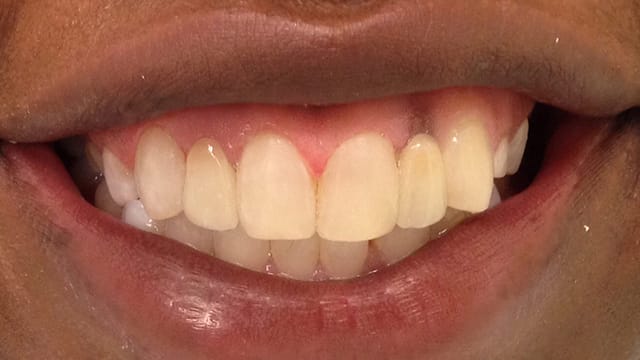

Below is a few examples of what DENTAL IMPLANTS can do for you and your smile!